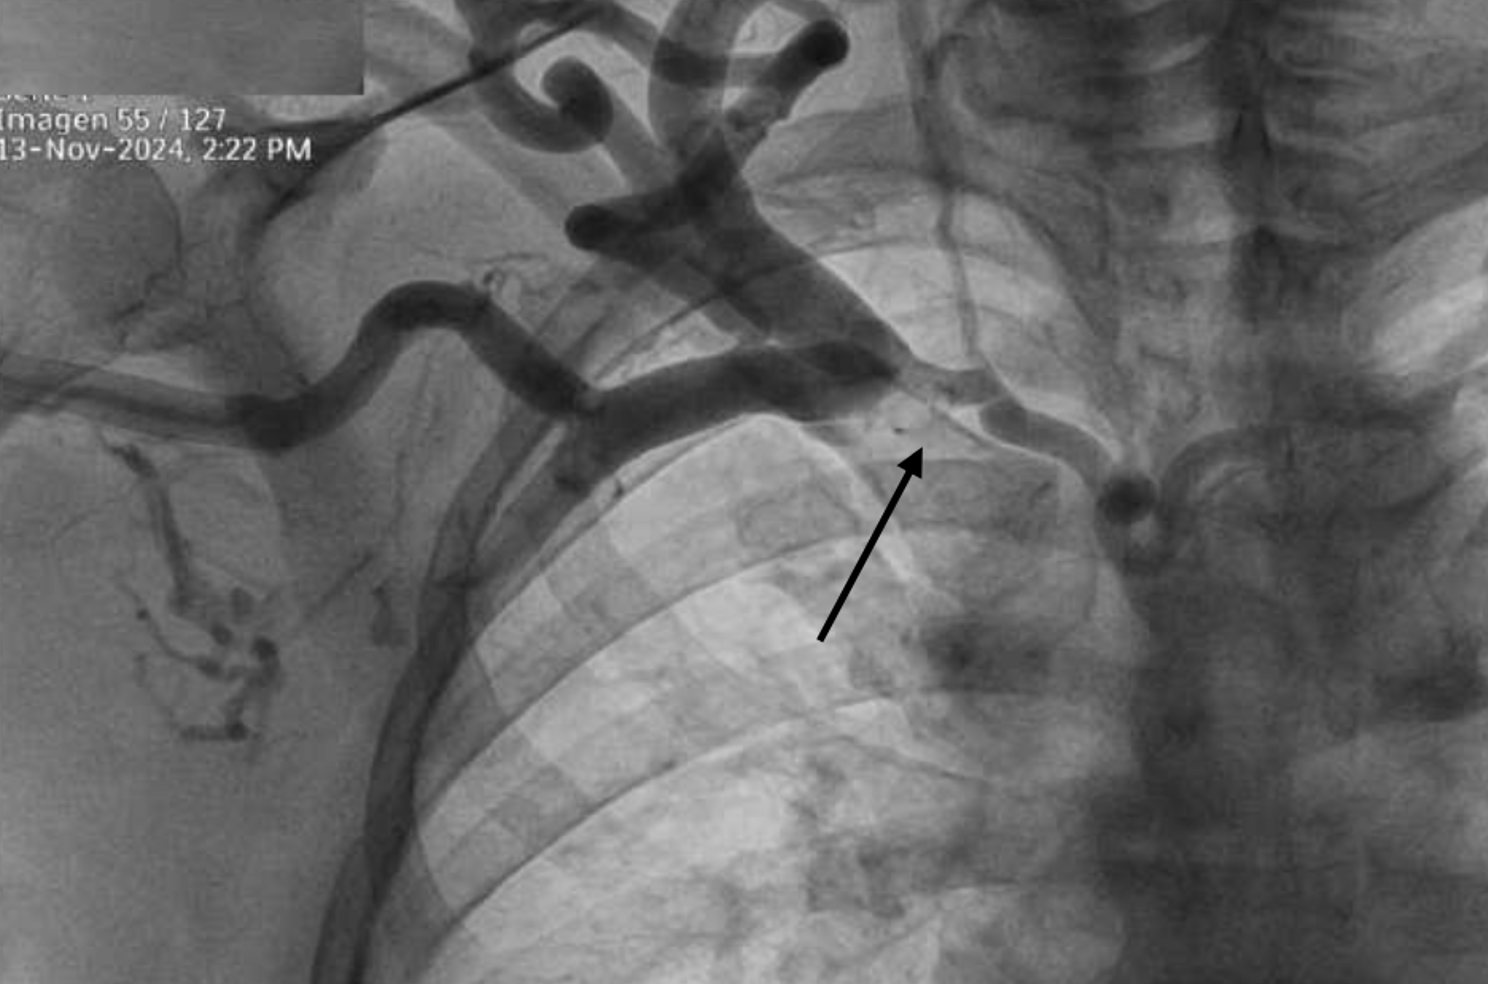

Diagnostic workshop: Interventional treatment revealed chronic stenosis in the right subclavian vein and innominate trunk.

Outcome: Interventional treatment using a stent graft and balloon angioplasty significantly improved access flow, reduced edema, and enabled continued hemodialysis sessions without complications.